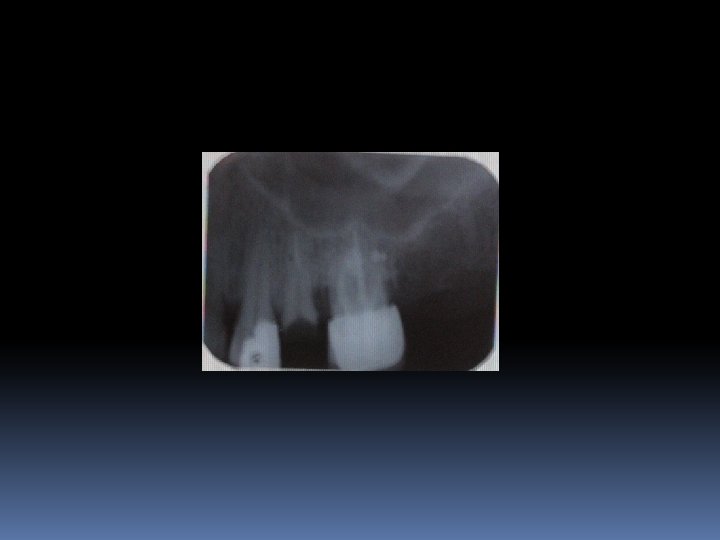

Post core yapım teknikleri: Kesim tamamlanınca ‘Peezo’ adı verilen mikromotor ucu, restorasyonu yapılacak dişin periapikal filmi üzerine tutularak, elde edilmek istenilen kanal boyutu işaretlenir.

Post core yapım teknikleri: Daha sonra işaretli noktaya ulaşıncaya kadar yavaş tur kullanılarak peezo ile istenilen boşluk elde edilir. Bu boşluk istenilen çapa çıkarılana kadar sırasıyla kalınlaşan gates glidden ya da peezo frezler kullanılır. DİKKAT SAKIN AEROTOR KULLANMAYIN.